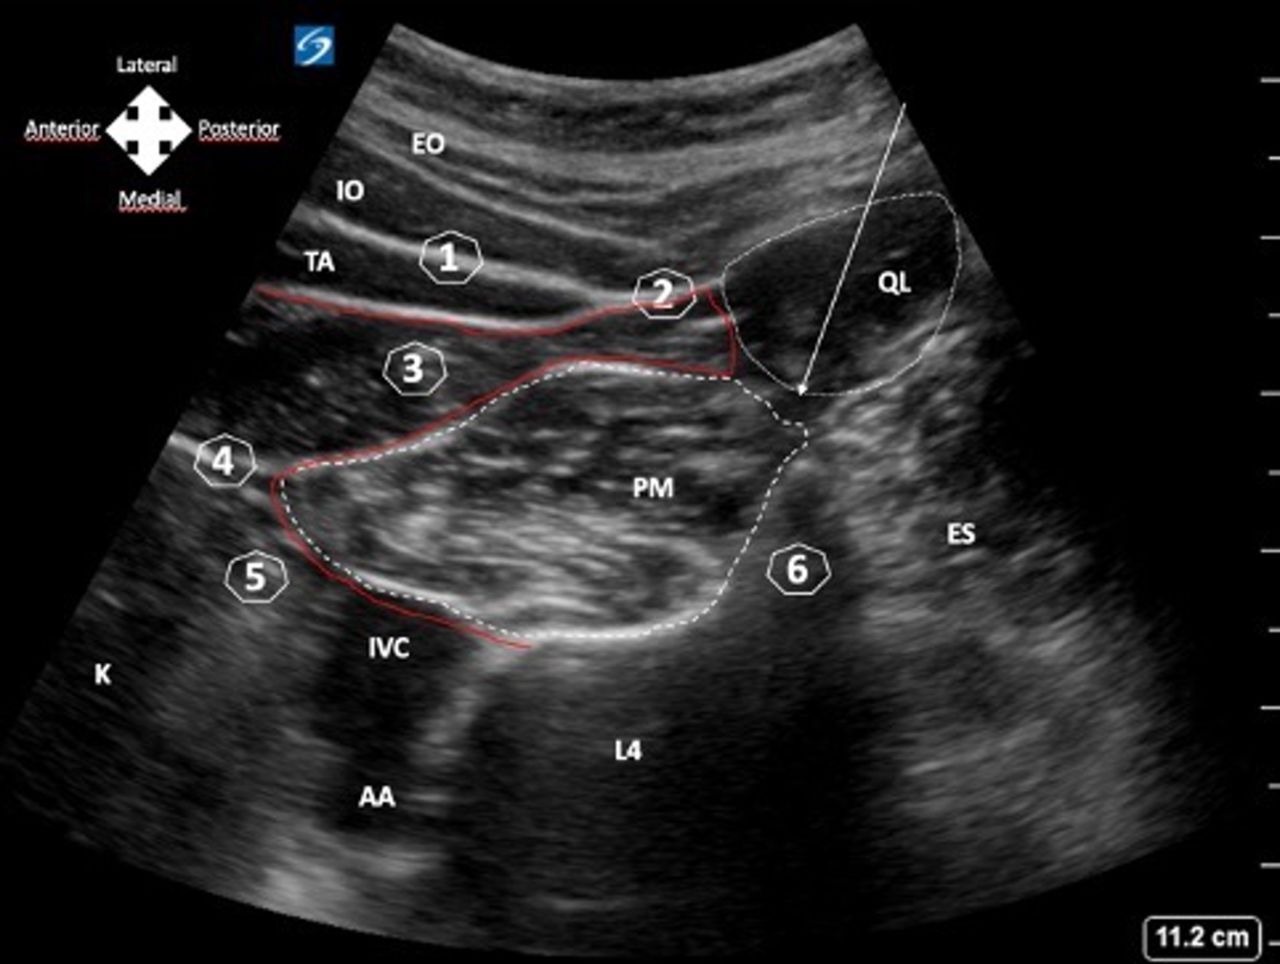

Quadratus Lumborum Block

A

30 mL each side should block most of anterolateral abdominal wall

Curvilinear probe transverse just cephalad to iliac crest

Hip flexed

Needle medial to lateral

QL approaches

Lateral similar to TAP

Posterior: fascial plane posterior to QL (hope local spreads anteromedially)

Anterior: LA between QL and PM. Most effective/best spread cephalad